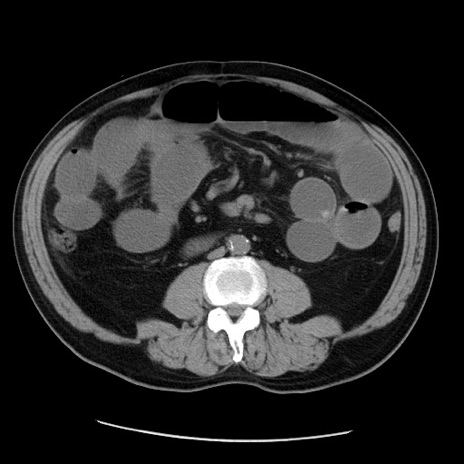

症例20(横断像)

【症例】 60歳代男性

【主訴】 腹部膨満、嘔吐

【現病歴】5日前頃より倦怠感を認め食事量減少し4日前の朝嘔吐、食事摂取困難となった。 3日前近医受診し点滴施行され整腸剤などを処方された。 当日他院を受診し、腹部膨満著明、炎症反応の上昇(CRP10.8、WBC11200)あり、紹介受診となる。

【身体所見】 意識JCS1 受け答えがはっきりしないBP 111/57mHg、 P 67bpm、、BT35.2°C、SpO2 97%(RA)、 腹部:膨隆、打診で鼓音あり、全体的に圧痛有り、腸蠕動音(-)、反跳痛ははっきりせず。

【データ】WBC 11400、CRP 14.20